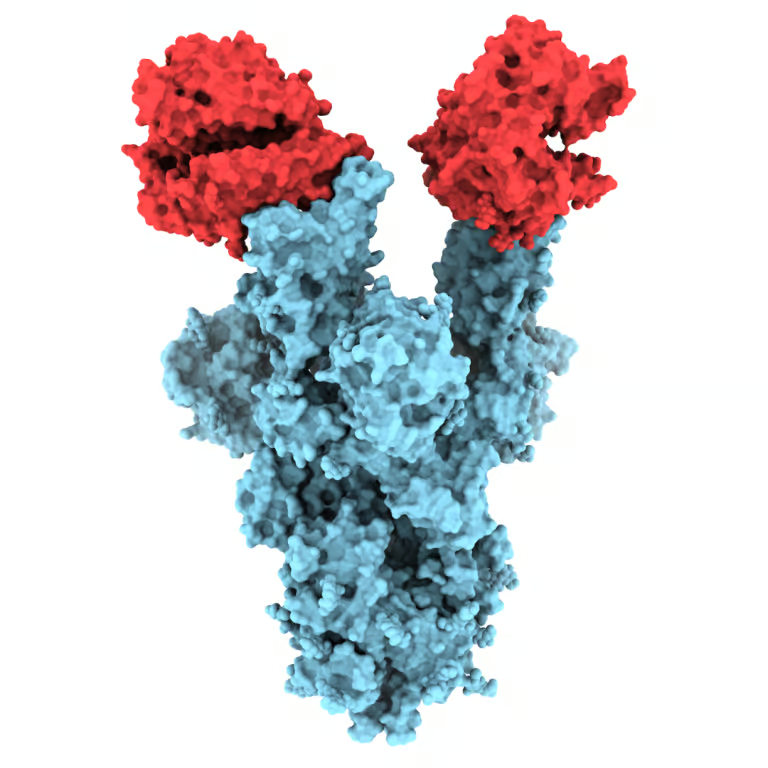

On Aug. 7, 2020, scientists at Scripps Research announced they had obtained high-resolution, atomic-scale details of the structure…

On Jul. 13, 2020, a team of researchers from Oxford University, the Rosalind Franklin Institute, Diamond Light Source…

On May 19, 2020, the National Institutes of Health (NIH) reported that researchers from the University of Texas,…